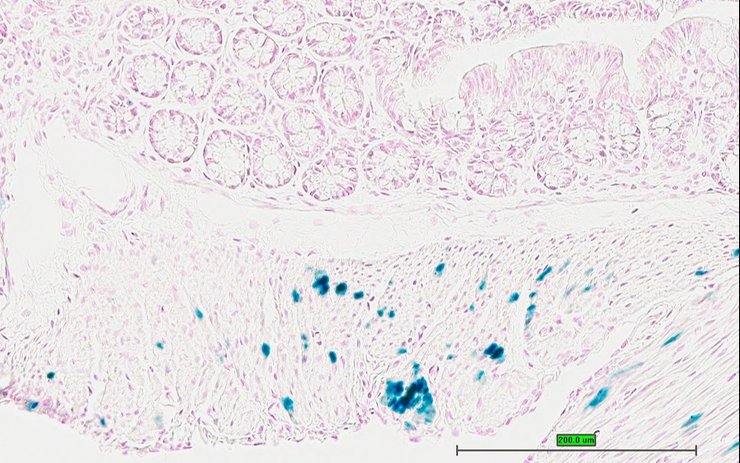

TS28: colon Present UC Davis_1875948

Specimen UC Davis_1875949: postnatal adult; Ppbptm1.1(KOMP)Vlcg/Ppbp+ (more )

Structure Level Pattern Image Note

TS28: colon Present UC Davis_1875949

TS28: colon Present UC Davis_1875965

Specimen UC Davis_1875966: postnatal adult; Ppbptm1.1(KOMP)Vlcg/Ppbp+ (more )

TS28: colon Present UC Davis_1875966